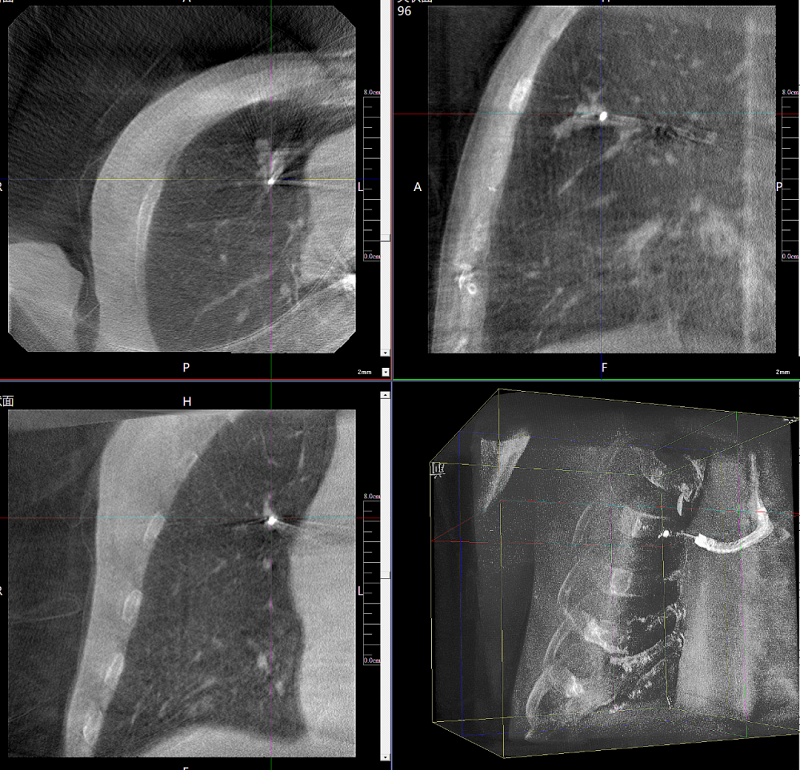

病例3:超声支气管镜下肺活检(80岁)

三维C形臂还可以创新性地应用在呼吸介入领域。例如,在经皮穿刺或经支气管镜肺结节活检、定位、消融等场景中,用于确认工具是否到达病灶、消融范围是否完全覆盖病灶等。

二维影像无法准确判断工具是否到达病灶

三维各切面影像都显示工具达到病灶内

二维C形臂提供的影像存在固有局限性,其成像原理是基于单一方位的投影,导致深部解剖结构信息缺失,且容易受到骨骼和组织的重叠干扰,使得部分病灶难以清晰显示,甚至被掩盖。相比之下,三维C形臂通过三维重建技术,可以获得类似CT的断层扫描图像,从而解决了二维影像的重叠问题。

医生能够利用这些三维图像,更直观、更深入地分析病变,进行全方位观察,例如:精确评估骨折复位情况、清晰显示内植入物的位置及其与周围组织的关系等。尤其在复杂骨折、脊柱手术、呼吸介入等临床场景中,三维C形臂提供的详细信息对手术导航和疗效评估至关重要。